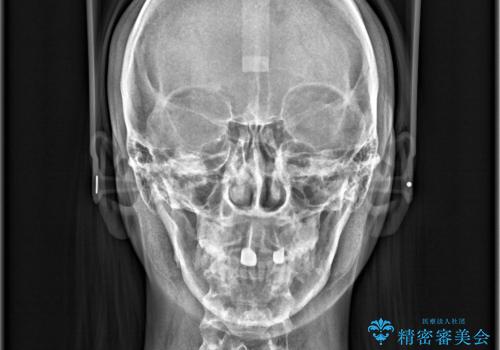

- ワイヤーで矯正した後戻りをマウスピースで治そうとしたが、使えなかったため再度ワイヤー矯正希望で来院されました。

装置はハーフリンガルを選択しています。

矯正としてはマウスピースでできましたが、患者さんの希望でワイヤー(ハーフリンガル)で矯正を行いました。

右下1が歯肉退縮していたため、アーチを拡げないように歯と歯の間を削って隙間をあけて並べています。